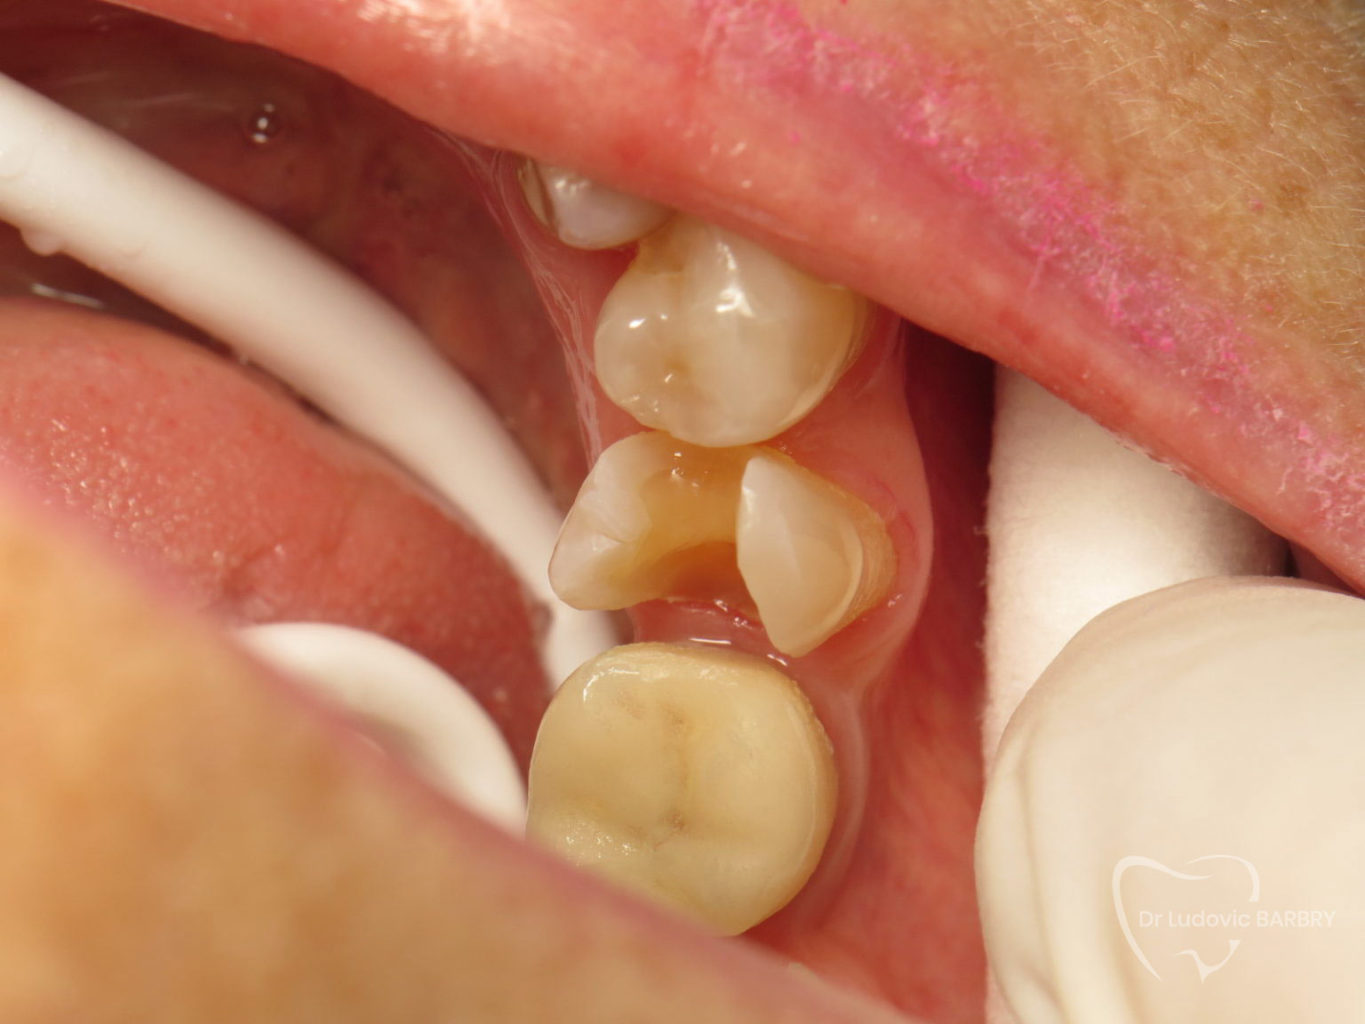

Inlay / Onlay céramique

Les inlays et les onlays sont des alternatives aux plombages ou aux résines de volume important. Il s’agit d’une technique moderne d’obturation qui permet d’éviter une prothèse beaucoup plus mutilante pour la dent et préserve l’intégrité de la dent en évitant les récidives de caries.

Cette pièce en céramique est fabriquée sur mesure et posée dans la séance grâce aux techniques modernes de CFAO (conception et fabrication assisté par ordinateur) que nous disposons au sein du cabinet.